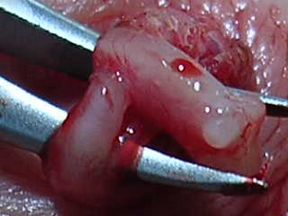

Of the four patients on whom I performed the VasClip procedure in the presence of the founder of the company, two experienced early failure. This 50% early failure rate is not acceptable and I no longer perform the VasClip procedure. The other two patients became sperm-free, but they are aware of the other two early failures and they have been encouraged to have their semen checked periodically for the delayed reappearance of sperm (late failure). The photos below were taken during the repeat vasectomy (on 2/23/05) of a man who had experienced VasClip failure.

Section of the vas with VasClip intact lifted through a small scrotal opening. The section was removed ...

...and one can barely see the opening of the cut vas. Water passed through the vas even before the VasClip was removed, confirming the patency (openness) of the vas.